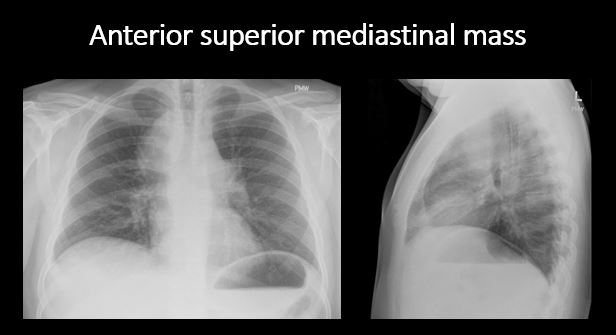

There is a mass or other abnormal density in or overlying the mediastinum. [Yes/No]

There is an abnormality in the retrosternal, retrotracheal, or retrocardiac space on the lateral view. [Yes/No]